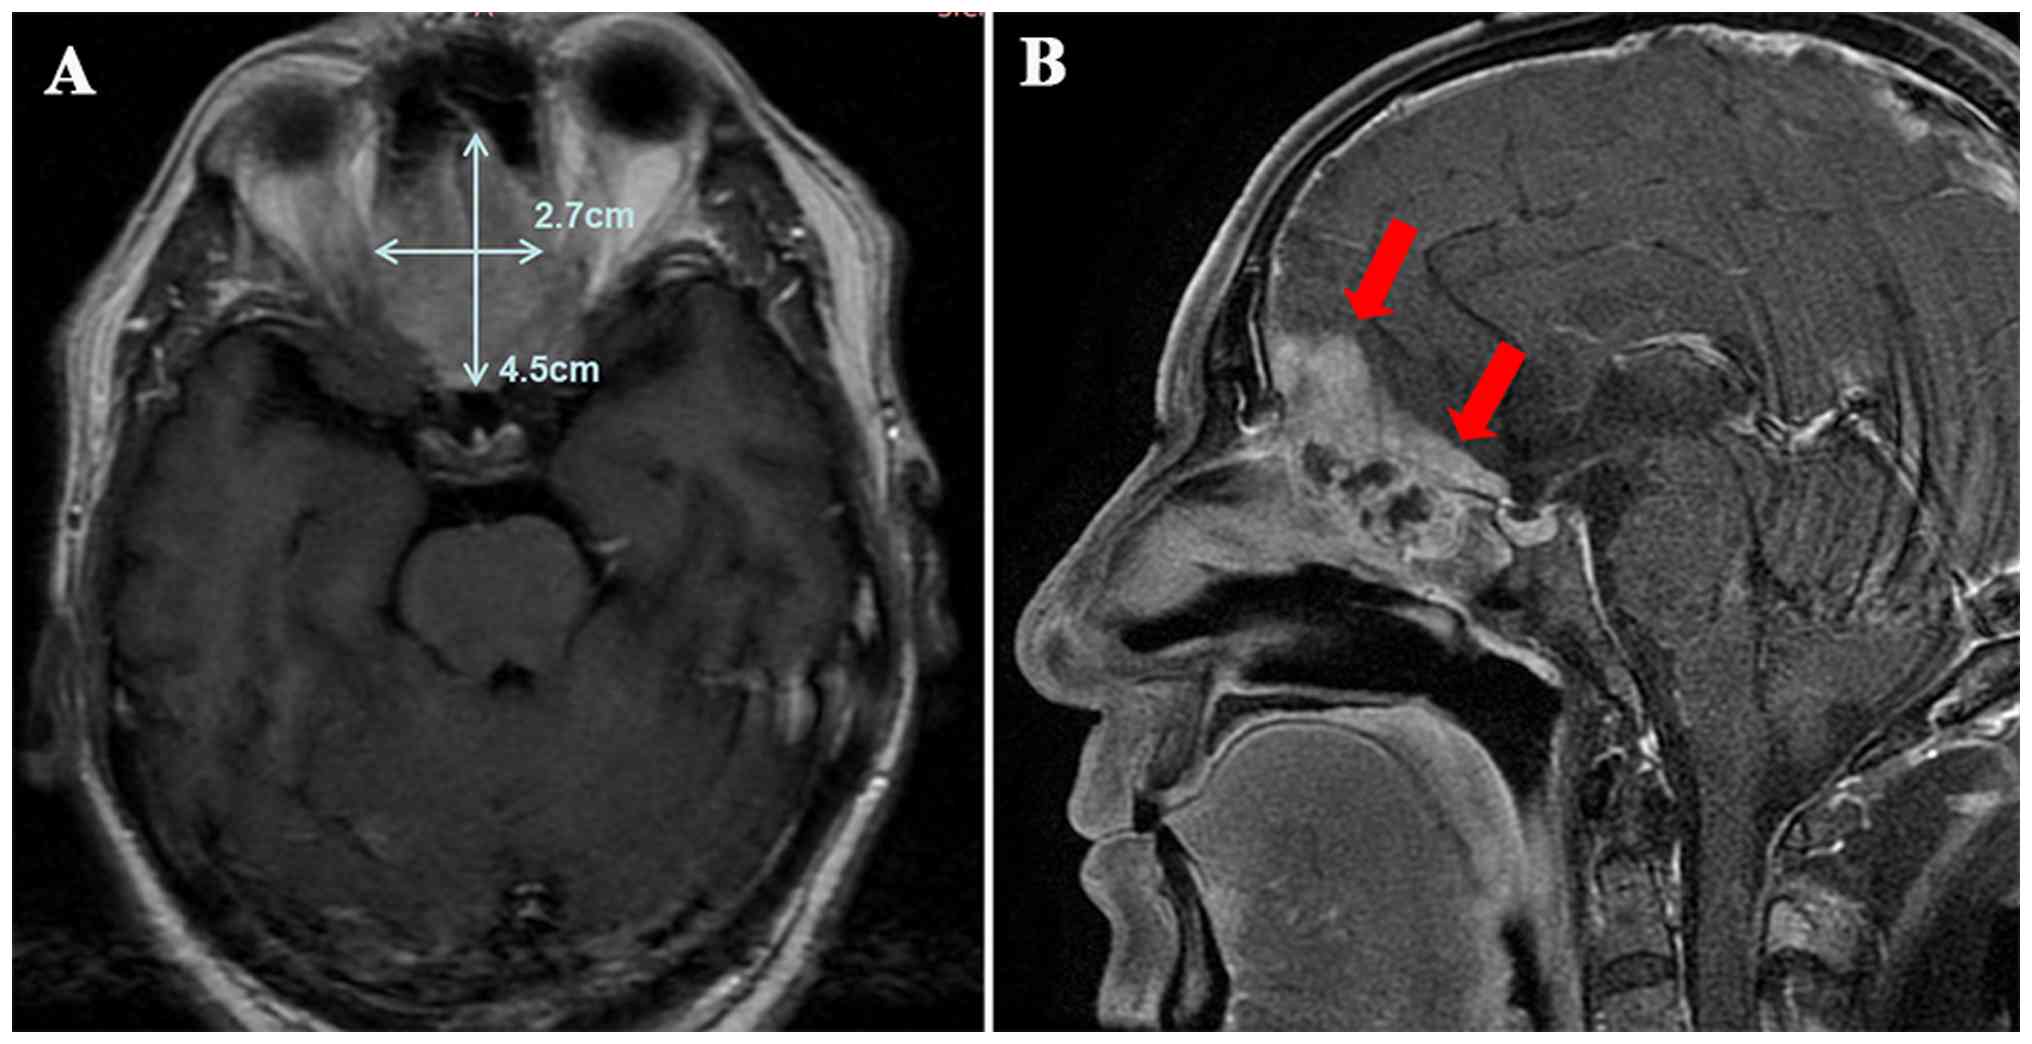

During treatment, the patient underwent MRI at each follow-up at a fixed interval of 2–3 months (sometimes according to their personal schedule). At the 11-month follow-up after the initiation of chemoimmunotherapy (February 2025), MRI (T1-weighted contrast-enhanced sequence) showed significant tumor progression compared with the scan performed at the 7-month follow-up. The longest diameter of the ethmoid sinus lesion had increased from 26.1 to 32.1 mm, with ill-defined boundaries and expanded invasion into surrounding tissues, which was consistent with the progressive disease based on the Response Evaluation Criteria in Solid Tumors 1.1 (RECIST 1.1) (Fig. 6). Following disease progression, the patient received anlotinib (12 mg once daily for 2 weeks on and 1 week off, with 3 weeks per cycle) and local interventional therapy to relieve symptoms, but subsequently developed intracranial and pulmonary metastatic progression. After that, the patient chose not to return for regular follow-up visits and was managed with best supportive care, being admitted to the hospital only when severe complications (fatigue, infection and vomiting) developed.

Follow-up assessment of tumor

progression based on Response Evaluation Criteria in Solid Tumors

1.1 criteria (progressive disease, defined as an increase of ≥20%

in the longest diameter of target lesions compared with the

baseline or the last non-progressive assessment, with an absolute

increase of ≥5 mm). (A) Axial view of contrast-enhanced T1-weighted

MRI at the 5th month of follow-up. An enhanced soft-tissue signal

was observed in the ethmoid sinus, with a measured tumor longest

diameter of ~26.5 mm. A clear separation between the tumor and the

orbit was noted (indicated by the red arrow). (B) Axial view of

contrast-enhanced T1-weighted MRI at the 7th month of follow-up.

The shape and scope of the enhanced soft tissue signal in the

ethmoid sinus were almost consistent with those at the 5th month,

with a measured tumor longest diameter of ~26.1 mm. A clear

separation between the tumor and the orbit remained visible

(indicated by the red arrow). (C) Axial view of contrast-enhanced

T1-weighted MRI at the 11th month of follow-up. The enhanced soft

tissue signal in the ethmoid sinus was notably larger than

previously, with a measured tumor longest diameter of ~32.1 mm (an

increase of 23.0% and an absolute increase of 6.0 mm compared with

the 7th month, meeting the progressive disease criteria). The tumor

showed ill-defined boundaries with surrounding tissues, suggesting

an expanded invasive range of the tumor. MRI, magnetic resonance

imaging.

Figure 6.

Follow-up assessment of tumor progression based on Response Evaluation Criteria in Solid Tumors 1.1 criteria (progressive disease, defined as an increase of ≥20% in the longest diameter of target lesions compared with the baseline or the last non-progressive assessment, with an absolute increase of ≥5 mm). (A) Axial view of contrast-enhanced T1-weighted MRI at the 5th month of follow-up. An enhanced soft-tissue signal was observed in the ethmoid sinus, with a measured tumor longest diameter of ~26.5 mm. A clear separation between the tumor and the orbit was noted (indicated by the red arrow). (B) Axial view of contrast-enhanced T1-weighted MRI at the 7th month of follow-up. The shape and scope of the enhanced soft tissue signal in the ethmoid sinus were almost consistent with those at the 5th month, with a measured tumor longest diameter of ~26.1 mm. A clear separation between the tumor and the orbit remained visible (indicated by the red arrow). (C) Axial view of contrast-enhanced T1-weighted MRI at the 11th month of follow-up. The enhanced soft tissue signal in the ethmoid sinus was notably larger than previously, with a measured tumor longest diameter of ~32.1 mm (an increase of 23.0% and an absolute increase of 6.0 mm compared with the 7th month, meeting the progressive disease criteria). The tumor showed ill-defined boundaries with surrounding tissues, suggesting an expanded invasive range of the tumor. MRI, magnetic resonance imaging.